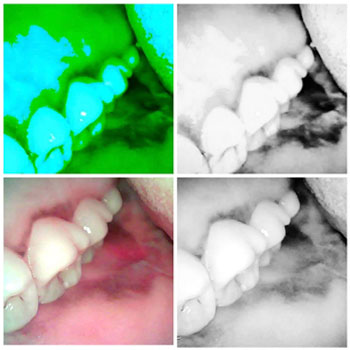

clinical Image and Image of the lesion Under the influence of Blue light, we can appreciate the difference in the extent of the lesion under white light and blue light. The blue light used with low intensity.

Clinical Image and Blue light image with High intensity of light, Both Images are filtered for better appreciation

With Low intensity of light, with high intensity of light , we can appreciate the reflection with enamel which is adjacent to the lesion, thus masking some part of the lesion

same lesion with the camera in the device with low intensity of light